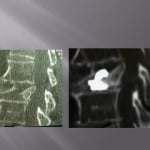

Vertebroplasty in the case of a fracture on posterior material implants

This type of vertebral fracture raises the problem of the entrance way and of the reduced visibility in lateral scopy of the filling of the secondary vertebral at the artrodesis material. The scannographic volume acquisition and the spotting has a large importance to guide the progress of the trocar without being blocked by the arthrodesis screws. The trocar path is outside the screws. An iterative scanner control checks the correct lateral position and the progression in the vertebrae to position at the level of the third anterior and third posterior. The filling is performed in the same way as standard vertebroplasty, the visualization of the cement by continuous lateral scopy is blocked by the osteosynthesis material, for this reason the injection must be done very carefully by alternatively controlling with scanner cuts the correct diffusion of the cement. The scanner control can also be blocked by the artifacts of the osetosynthesis material. Moreover in the cases of osteopenic fractures on arthrodesis, a low density line can exist around the screws showing a potential mobility of the material. In this case, the scanner guide can be very useful to position the tip of the trocar in front of this line. Thus, the vertebroplasty has the additional function to fix the intra vertebral corporeal arthrodesis.

Only the scannographic cuts allow to confirm the correct diffusion around the screws. The clinical results in out series are stackable to the vertebroplasties in the frame of the hyperalgic osteopenic fractures.